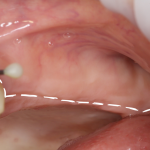

Все разные, у каждого из нас есть особенности анатомического строения, делающие его непохожим на других людей. Применительно к теме нашей беседы, можно сказать, что гайморова пазуха при одинаковом внешнем объеме верхней челюсти, у разных пациентов может быть разного размера: у кого-то она очень большая и воздушная (т. н. «гиперпневматизация»), у кого-то, наоборот – маленькая и склерозированная («гипопневматизация»). Это индивидуальная анатомическая особенность. К примеру, на рисунках 3 и 4 представлены ортопантомограммы двух пациентов одного возраста и пола с похожими клиническими случаями. На рисунке 3 мы видим небольшого размера верхнечелюстную пазуху (обозначена черной пунктирной линией), в то время как на рисунке 4 – выраженная гиперпневматизация верхнечелюстной пазухи (границы верхнечелюстной полости обозначены белой пунктирной линией).

Рисунок 3, 4. Расположение и объем гайморовой пазухи – индивидуальная анатомическая особенность. Слева – гипо-, а слева – гиперпневматизация придаточных пазух носа.